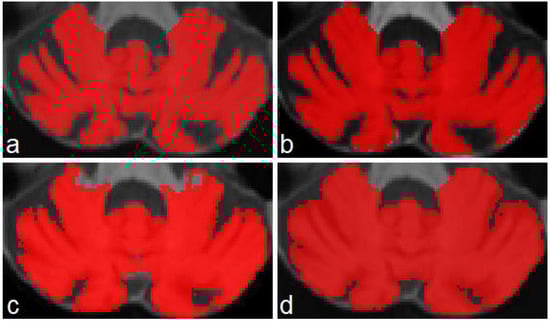

Despite the excellence of the existing methods and the reported results, none of this research is oriented to correctly segment and determine all important fissures in cerebellum of patients with neurodegenerative diseases. Figure 1 shows a comparison between segmentations produced by CERES and ACAPULCO for one magnetic resonance from a SCA2 patient with severe cerebellar atrophy. It can be seen that CERES made a better recognition of increased fissures than ACAPULCO, however, some of them have been incorrectly classified as cerebellar tissue. This phenomenon must be related to the training images and labels for both methods, but it should have great impact on the calculation of volumes for the affected parts. As the fissures are classified as cerebellar tissue, the resulting volumes should be larger than the actual ones, giving an incorrect idea of the atrophy produced in the patient’s cerebellum. Images were generated with ITK-Snap software [21], CERES segmentation was obtained through the web portal (https://www.volbrain.upv.es/, accessed on 5 December 2021), and ACAPULCO segmentation was obtained by using a docker container shared by the authors in the original paper [1].

Figure 1. Comparison between segmentations on MRI of SCA2 patient. In (a) the original imaging, in (b) segmentation produced by ACAPULCO, and in (c) segmentation obtained by CERES.